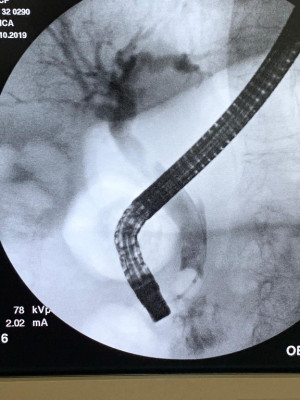

Cálculo gigante por coledocoliatisis